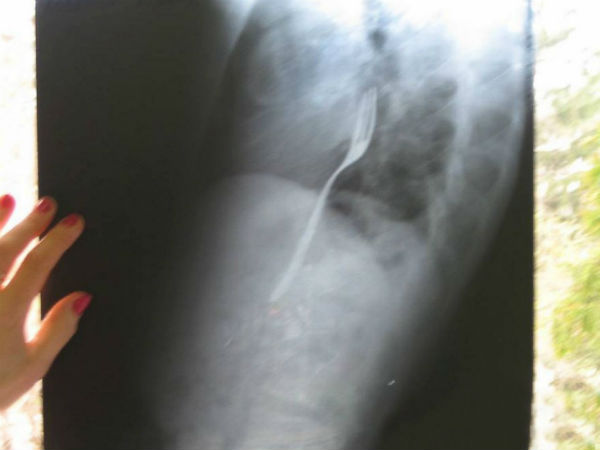

மனித உடலில் கண்டுபிடிக்கப்பட்ட வித்யாசமான பொருட்கள்

குழந்தைகள் பல்பம், மண் எடுத்து வாயில் போட்டுக் கொள்வதை பார்த்திருப்போம். ஆனால் இங்கே மருத்துவர்களையே அதிர்ச்சியில் உறைய வைத்த பல விஷயங்களை முழுங்கியிருக்கிறார்கள்.

மருத்துவ உலகம் எப்போதும் தனக்குள்ளே ஆச்சரியங்களை நிரப்பி வைத்திருக்கும் விந்தையான உலகம். தொழில்நுட்பங்களைத் தாண்டி மருத்துவ உலகில் நடக்கும் சில வேடிக்கையான விஷயங்களும் நம்மை ஆச்சரியத்தில் ஆழ்த்திடும். குழந்தைகள் பல்பம்,மண் எடுத்து வாயில் போட்டுக் கொள்வதை பார்த்திருப்போம். ஆனால் இங்கே மருத்துவர்களையே அதிர்ச்சியில் உறைய வைத்த பல விஷயங்களை முழுங்கியிருக்கிறார்கள்.

ப்ளாஸ்டிக் ஃபோர்க் :

ஃபோர்க் ல சாப்பிட சொன்னா ஃபோர்க்கையே சாப்பிட்டா இப்டித்தான். ஜான் மான்லே என்பவர் தொடர்ந்து தனக்கு மூச்சு வாங்குவதாகவும் இருமல் இருப்பதாகவும் மருத்துவமனைக்கு சென்றிருக்கிறார்.

சோதித்த மருத்துவரக்ள் அவரது மூச்சுக்குழாயில் பெரிய கட்டி வளர்ந்திருப்பதாக தெரிவித்தனர். அது புற்றுநோய்க்கட்டியாக இருக்குமோ என்றெல்லாம் சோதித்தனர். கடைசியில் ஆப்ரேஷன் செய்து அதை வெளியே எடுத்தபோது தான் உணவுக்குழாயில் இருந்தது கட்டியல்ல ப்ளாஸ்டிக் ஃபோர்க் என்று தெரிந்தது.